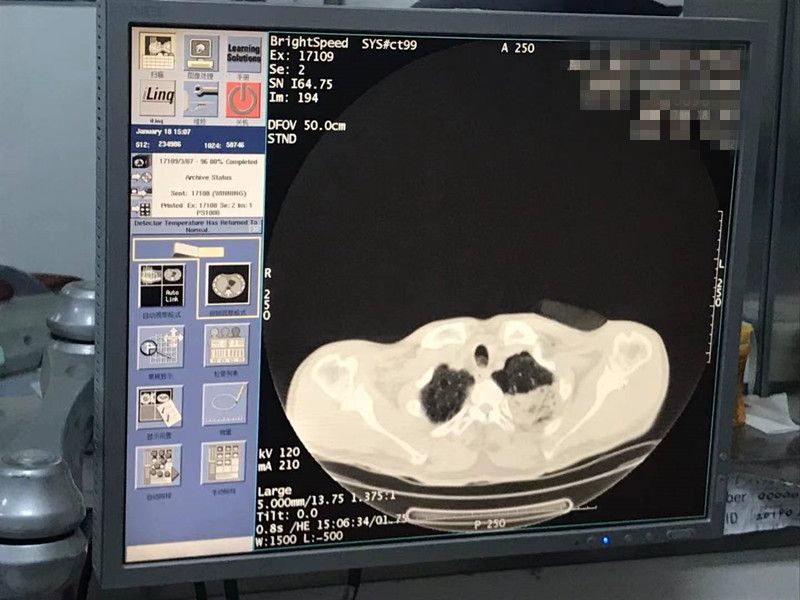

2021年1月份肺部氩氦刀手术

发布人:美国氩氦刀技术官方网站    发布时间:2021/9/22 15:39:30